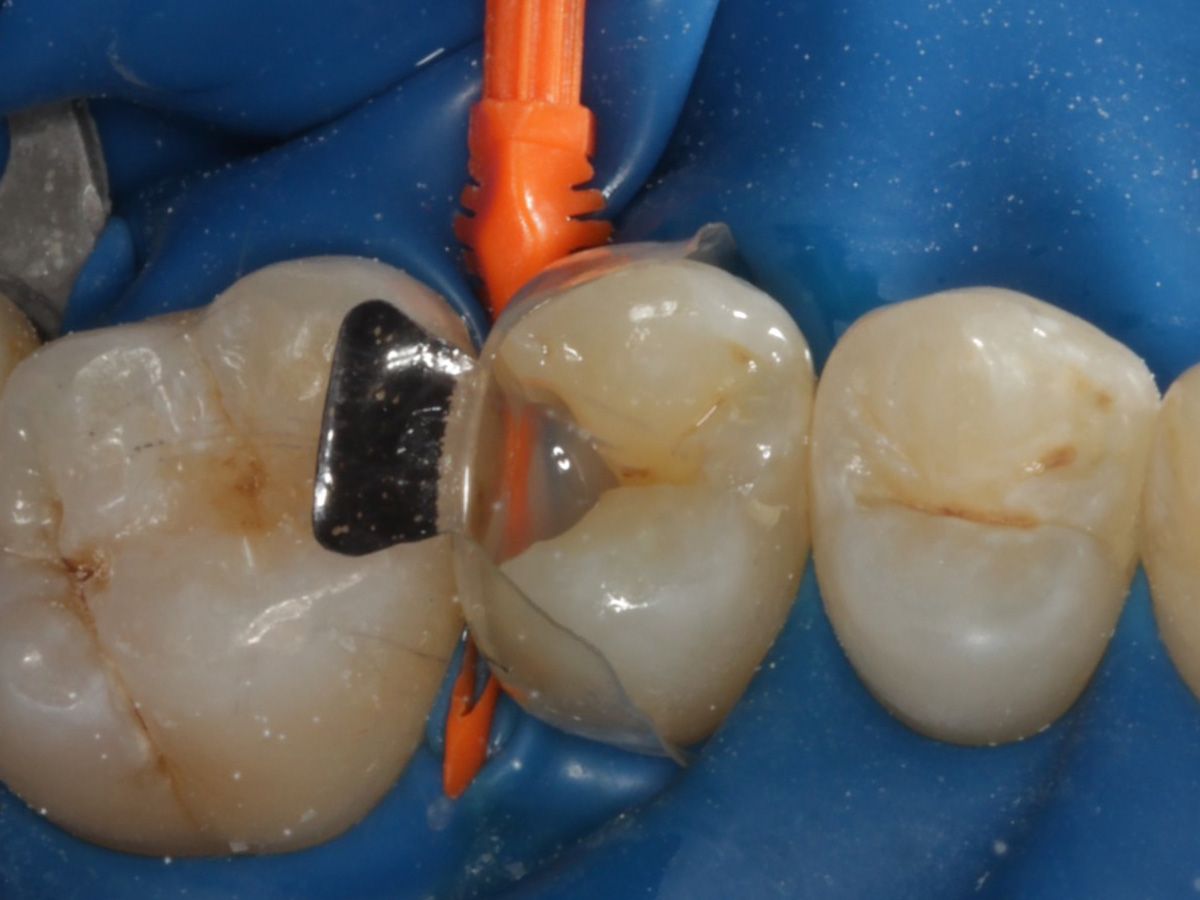

Abbildung 10

Nach Applikation der Matrize: Evolve Schwarz Prämolar- 7 mm; Schmelzätzung

Abbildung 11

Nach Spray und Trocknung der Kavität

Nach erneuter Applikation des Einkomponentenadhäsivs und tief approximal eines fließfähigen Bulkkomposits, der Lichthärtung, und der Applikation des Bioclear Diamond Wedges Medium